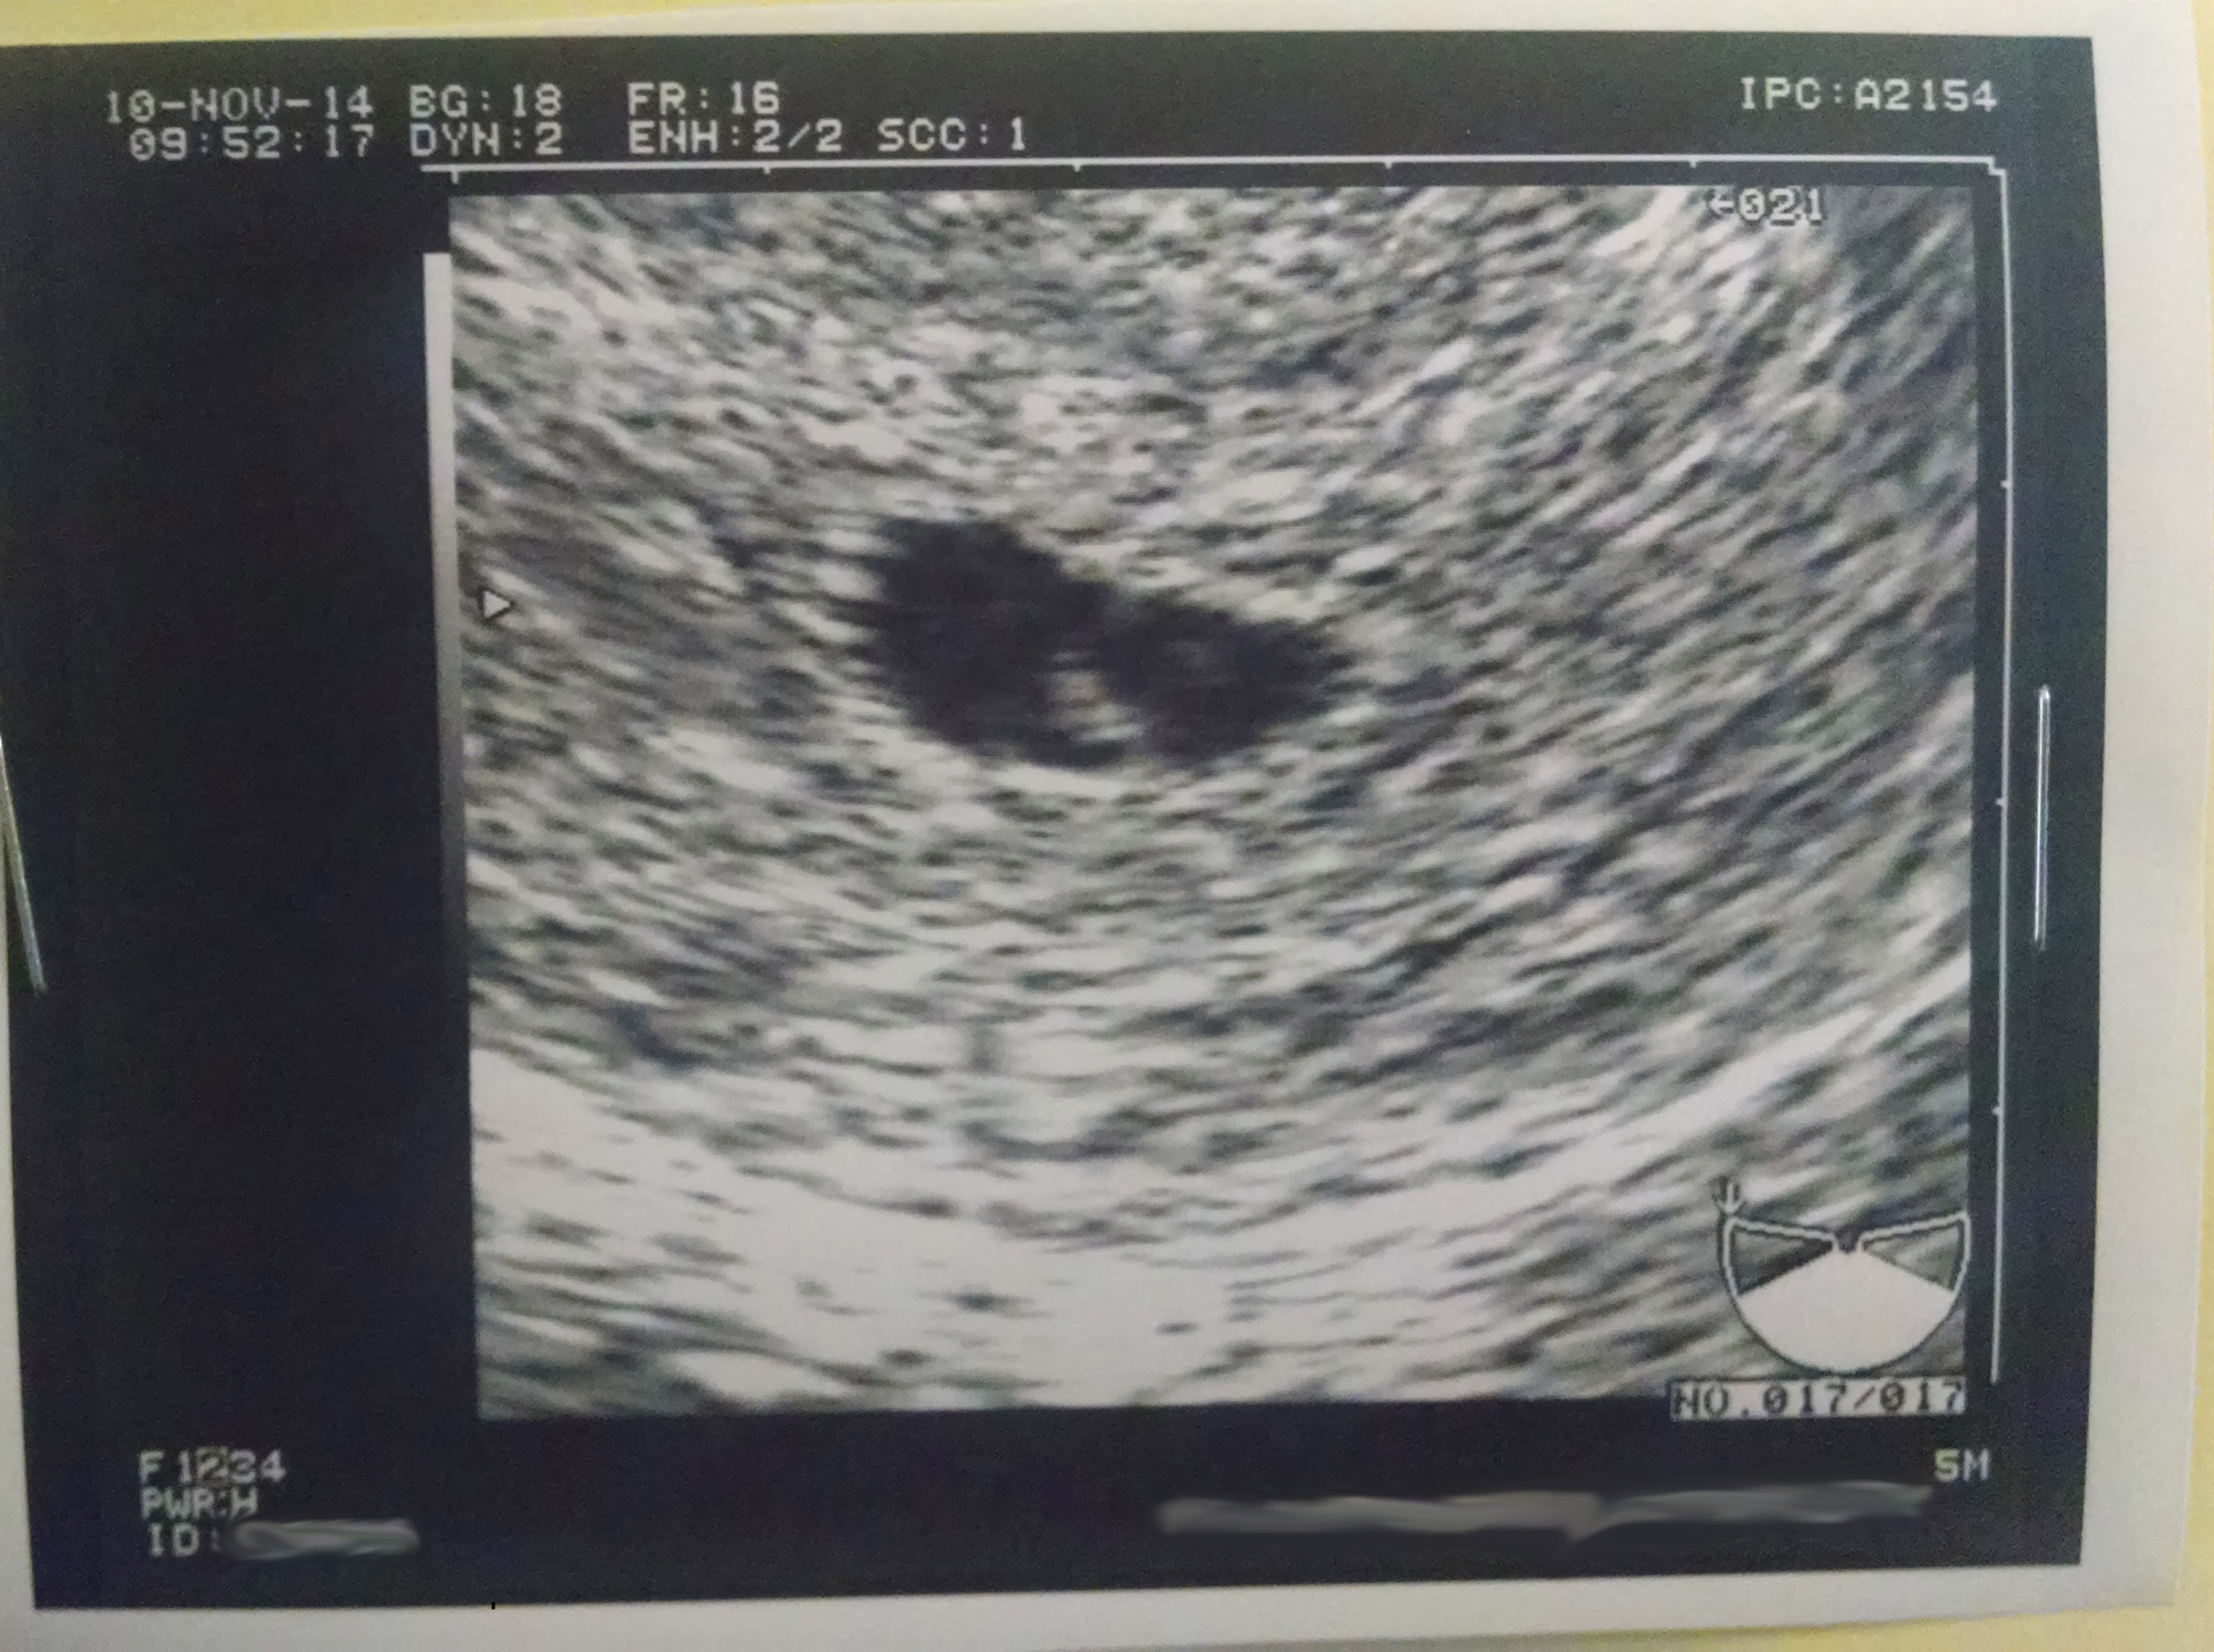

Yorkie babe has a heartbeat!

The ultrasound went perfectly. Baby measured right at 6 weeks 3 days and the HB was 125. We have another US in 2 weeks, where they'll give me my official due date and release me to a regular OB.

ETA: Baby's first picture!